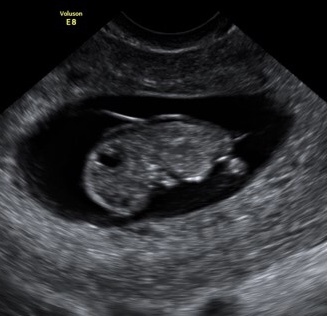

I had a private early pregnancy scan today and was told I am measuring around 9 weeks 3 days (dates would have me at 10 weeks 2 days but my periods are irregular).

At the scan we saw a heartbeat and was told everything looked fine however since being at home I have been looking at the pictures and worrying about the fluid behind babies neck.

Does it look enlarged to you? I know it is too early to really tell but does anyone have any experience?

I agree, it's impossible to tell. Pictures are blurred also, only they can get an accurate measurement, try not to worry or read into things. I'm the exact same and have done it thru my whole pregnancy and it drives you crazy lol. Enjoy and relax till told otherwise x

As PP have said, it's hard to tell this early. The scan will be zoomed so far as well.

Just looking at it without the measurements won't show anything